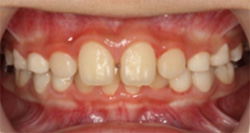

5、永久歯が生えてこない・おかしな位置から生えてきた

・前歯の生え変わりのタイミングで治療を行うことを推奨します。

永久歯が生えてこない理由にはさまざまありますが、その中の一つに「歯が生えるスペースが無いために生えてこれない」というものがあります。

特に最近では、上顎の発育不良により歯が生えてくるスペースを確保できないため、犬歯が八重歯となってしまっているケースを多く見かけます。

永久歯があるのに出てこれない(埋伏歯)状態の場合、その歯だけではなく、隣の歯の歯根吸収(歯根が溶かされてしまうこと)を起こすリスクが高いため、早い段階での対応が必要になります。